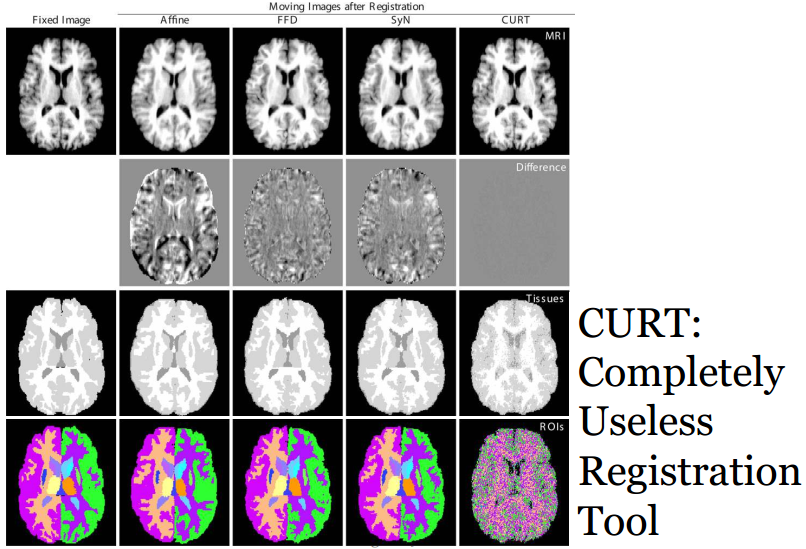

非常简单的形变配准算法:CURT

基于闭型解的非刚性配准算法来最大化秩相关约束Rank Correlation criterion。图像相似度和组织重叠度来的评价标准更好image similarity and tissue overlap scores。不需要仿射变换处理。